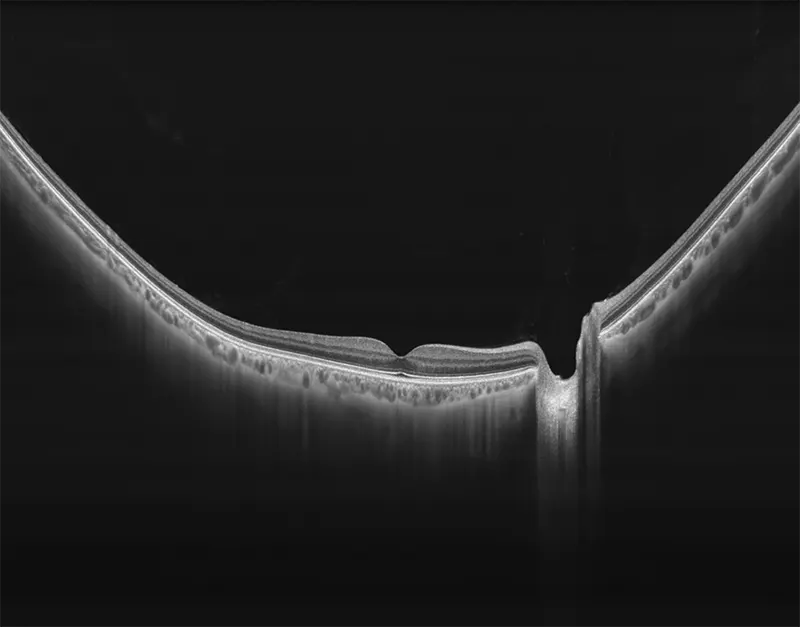

BMizar (BM-400K) es el OCT más potente de la industria con una fuente de barrido de 400 kHz. Su excepcional diseño óptico eleva la experiencia de la Angiografía OCT a un nivel sin precedentes. Con imágenes de alta definición de la retina, la coroides y el segmento anterior, cubre sin esfuerzo un área increíblemente grande en un solo escaneo (logrando un OCTA de 24 mm de ancho en solo 7-15 segundos).

Galería OCTs del TowardPi BMizar